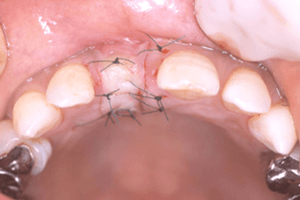

あごの骨にインプラントを埋め込みます。一次手術後、3~6ヶ月間の治癒期間をおくことで、インプラントと骨が強い力で結合します (オッセオインテグレーション)。この期間、仮の歯を使用できる場合もあります。歯ぐきを開いて人工の歯を取り付ける準備をします。この状態で、歯ぐきが治るまで1~6週間おきます。

歯ぐきが治った時点で型を取り、人工の歯を作ります。形や色などは患者さんに合わせて作製し、インプラントに取り付けます。

歯周病等で骨が失われた部位に人工骨や自家骨 (自分の骨) を移植し、骨の再生を図る治療のことで、歯周組織再生療法のひとつです。GBRは主に「インプラントしたいけれど骨の量が足りない」場合に行います。